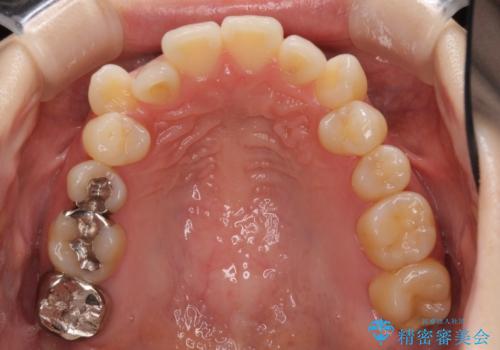

- 前歯のデコボコや八重歯の様になっていることを気にして来院された患者様です。

犬歯捻れて前方に飛び出しており、下顎前歯もそれに沿うようにデコボコとなっていました。

IPR(歯と歯の間を削る処置)によりスペースを獲得して上下顎前歯のデコボコを改善し、前歯が前方に突出しないように設定した上で、インビザラインにて矯正治療を行うこととしました。